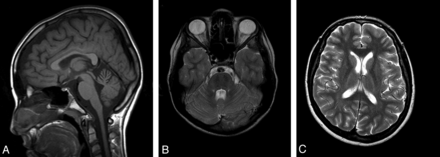

DTI

Visual evaluation of color FA maps revealed bilaterally smaller and displaced CSTs in the pons (Fig 2A, -B) in patients with ARSACS compared with control participants. The pyramids and CSTs in the midbrain were normal in location. The pons was mostly occupied by “left-to-right” direction-coded fibers of the TPF (Fig 2A). Tractography showed thickening of the TPF and interruption of the CST in the pons with relative thinning in the midbrain and medulla oblongata in the patients (Fig 2C, -D).

Directionally encoded color FA image of the same patient as in Fig 1 (A) shows that the CST (blue, long arrow) is smaller and displaced in the pons by “left-to-right” direction-encoded TPF (red, short arrow). Tractographies of CST (blue) and TPF (red) depict interruption of CST by thick TPF (C). Corresponding FA image (B) and tractography (D) of a sex- and age-matched control participant are also given.